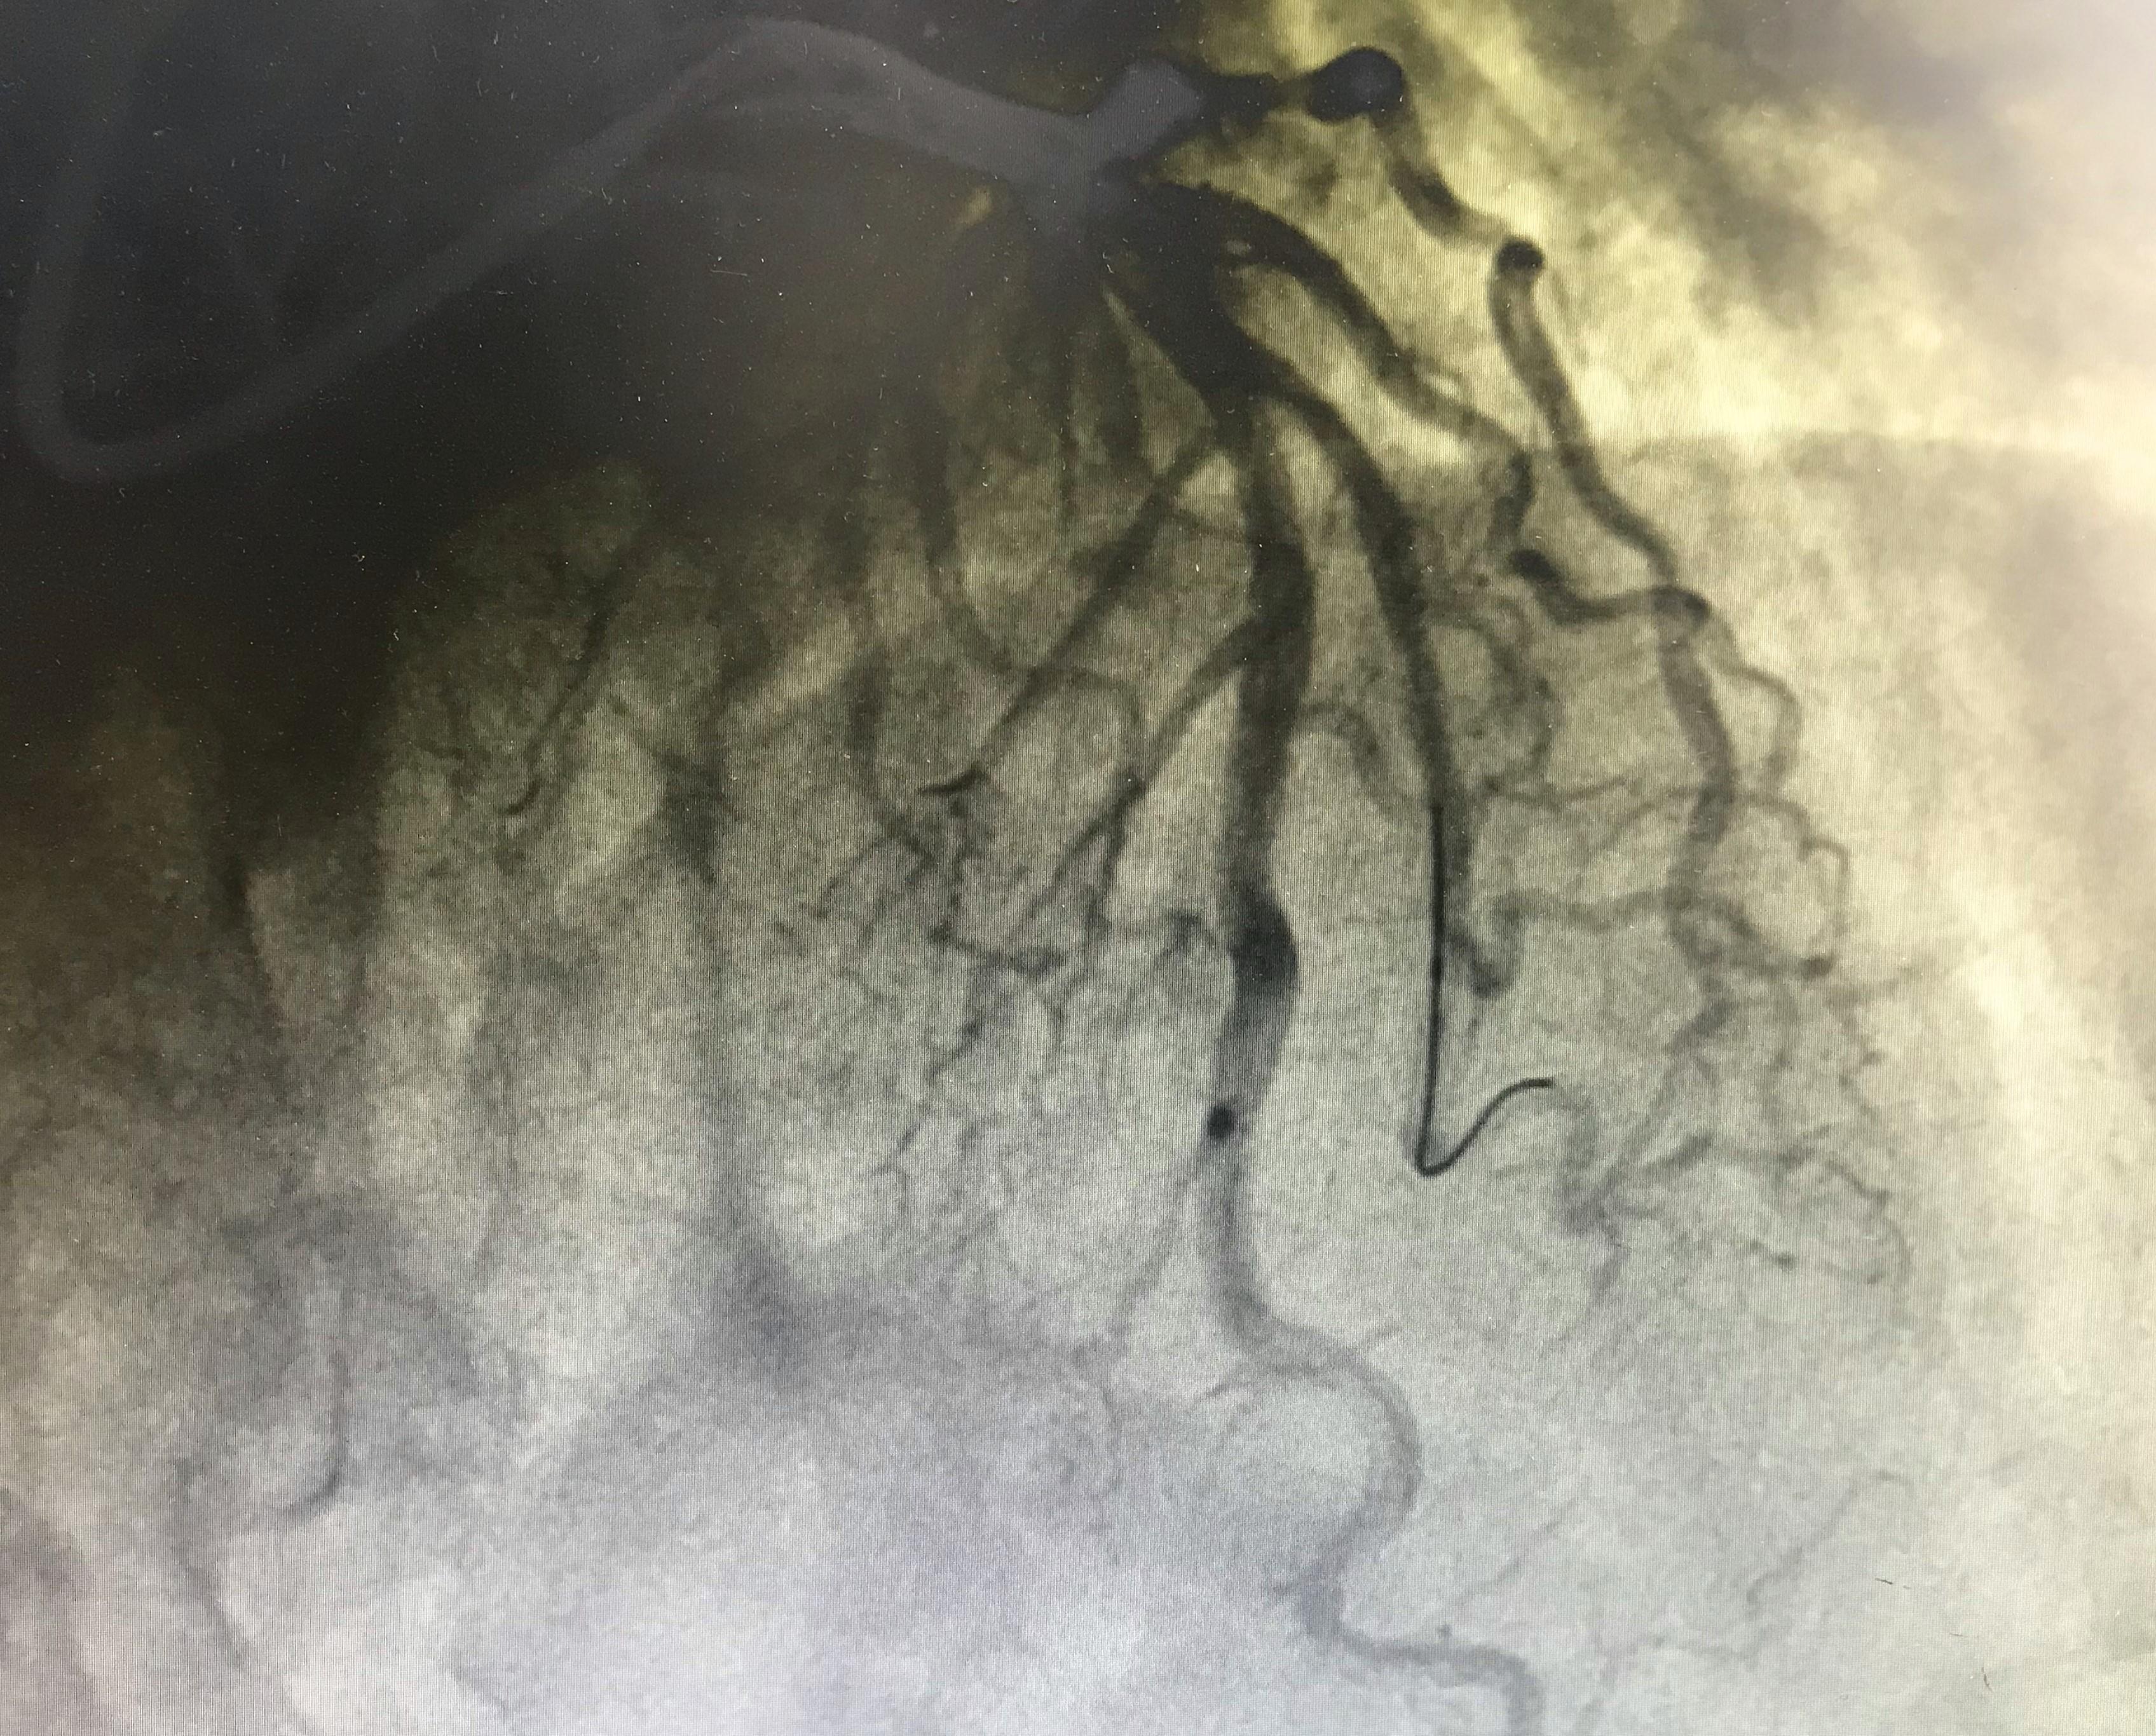

病因找到了,我们准备给他放支架把血管撑起来!先用球囊把严重狭窄的地方扩张开来,然后把比这段血管稍粗一点的支架,精准定位后,在狭窄位置扩张开,这样整根血管就完美如新啦!

文章插图

球囊对狭窄部位扩张后